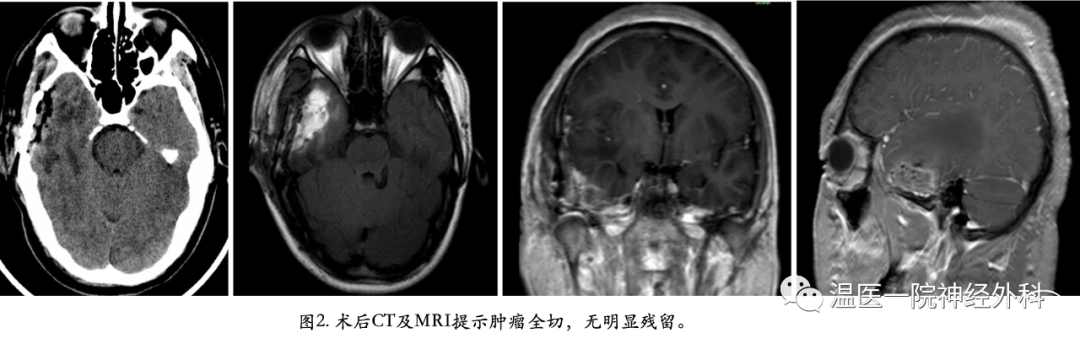

术后复查头颅CT及MRI(图2),提示病灶全切,无明显残留。